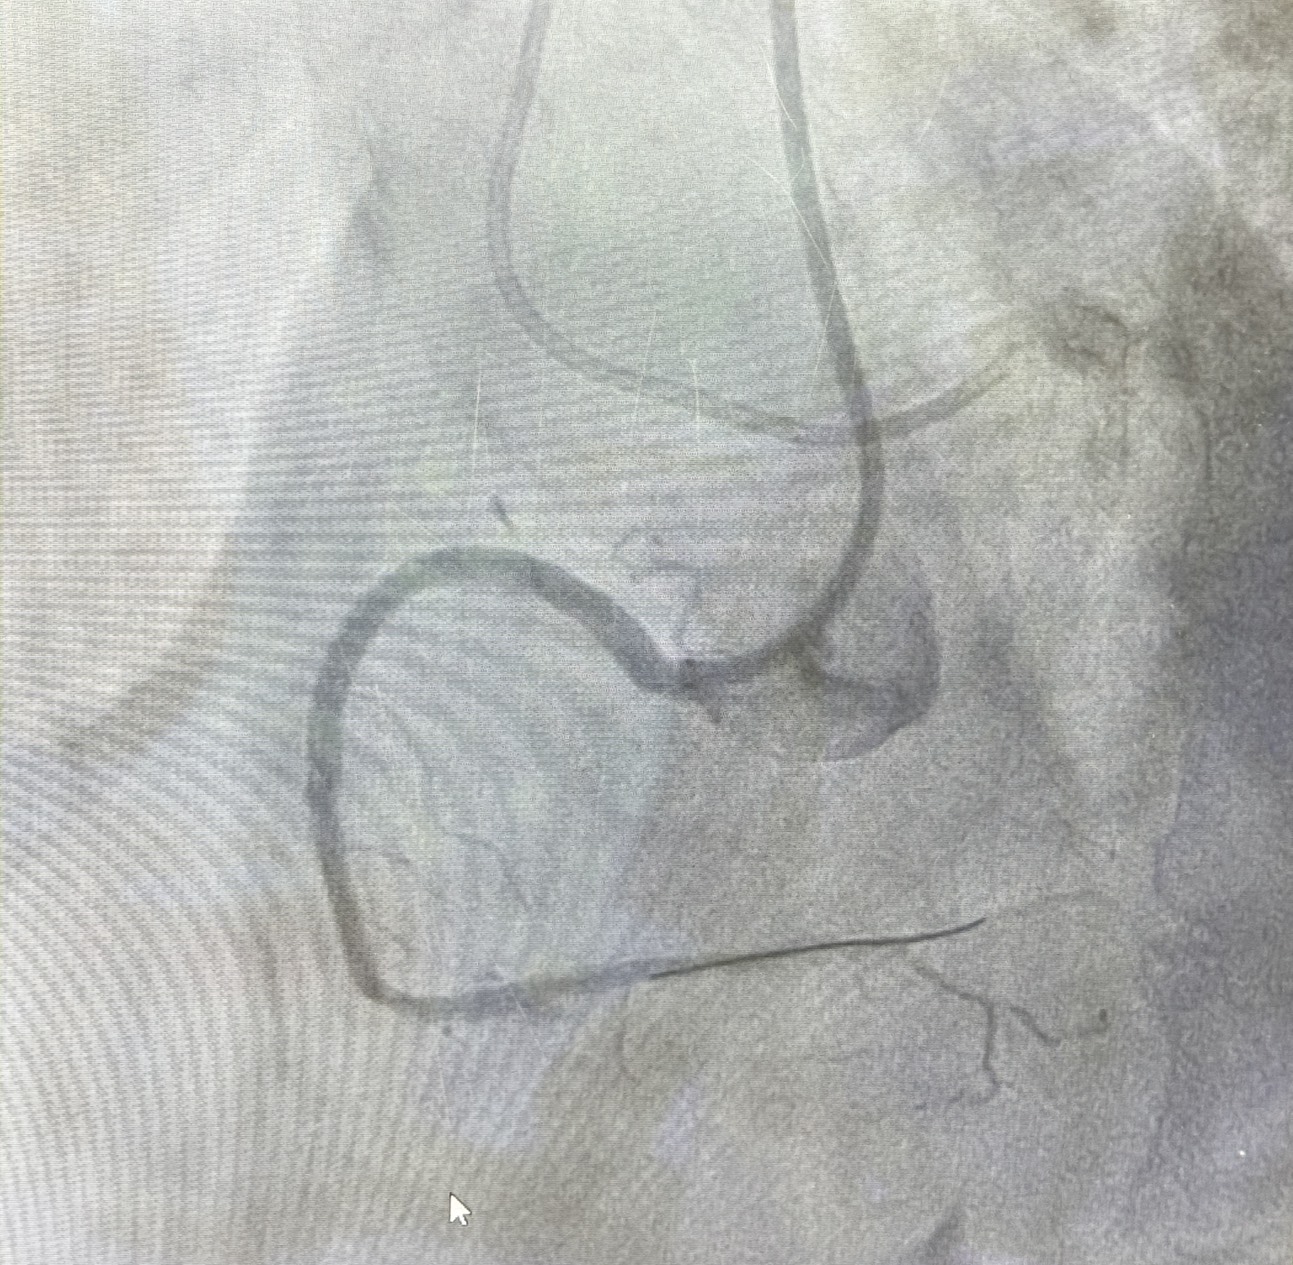

在冠狀動脈疾病治療上,蘇柏學醫師亦完成高難度的慢性冠狀動脈完全阻塞(CTO)介入治療。此類病灶技術門檻高、風險大,過去多需轉診至大型醫學中心,如今在麻豆新樓醫院即可完成血流重建,明顯改善病人長期心絞痛與活動受限的問題。